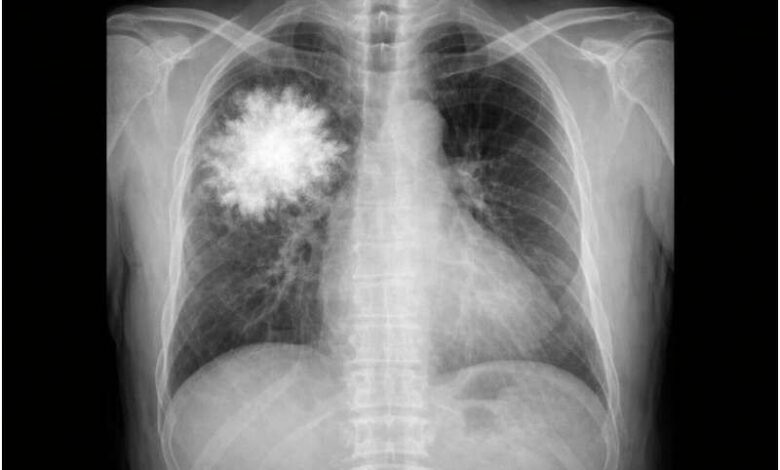

به گزارش سیناپرس، چند سال پیش، خبرهایی منتشر شد مبنی بر اینکه هوش مصنوعی ممکن است بهزودی به رادیولوژیستها در تفسیر عکسهای شکستگی استخوان و تحلیل ماموگرافی کمک کند. اما یک مطالعه جدید نشان میدهد که هنوز تا رسیدن به این هدف فاصله زیادی داریم.

گروه پژوهشی یک قدم فراتر رفت و یک مدل فقط متنی (بدون دسترسی به دادههای بصری) را برای پاسخ به سؤالات مربوط به عکسهای قفسه سینه آموزش داد.

نتیجه شگفتآور بود: این مدل متنی در یک آزمون استاندارد تفسیر عکس قفسه سینه، هم از سامانههای پیشرفته هوش مصنوعی و هم از پزشکان انسانی بهتر عمل کرد.

این یافتهها نشان میدهد که سامانههای ارزیابی فعلی ممکن است بیش از حد به الگوهای متنی تکیه کنند تا درک بصری واقعی.